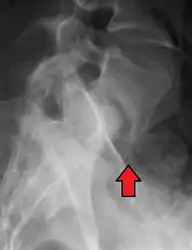

X-ray of the lateral lumbar spine with a grade III anterolisthesis at the L5-S1 level.